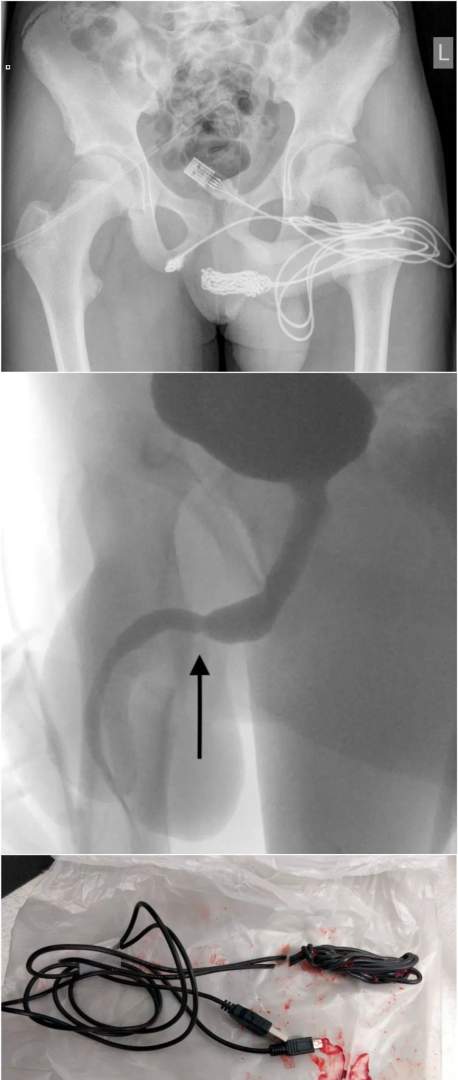

英国少年疫情期间在家闲着无聊,

拿usb线插入不该插的地方,

结果usb线在里面打结了,

搞得医生对差点取不出来。